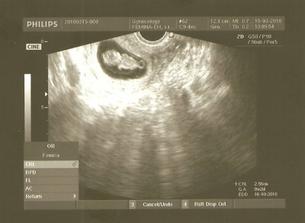

15.3.2010 - som objednaná na prvú poradňu, kde sa veľmi tešíme....takže poradňu máme za sebou, srdiečko nám bilo ako na technopárty :o), cez víkend nás premohla aj choroba, horúčky - 38,3 až 38,8 a k tomu aj bolesť hrdla....